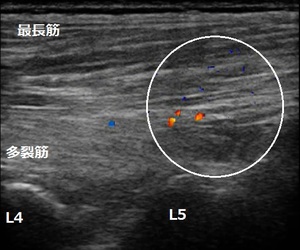

鶴ヶ島市 男性 腰痛 ぎっくり腰

左腰椎4,5関節部

男性に腰の前屈をしてもらうと痛くて出来ません。後屈は前屈ほど痛みません。うつ伏せになって上半身を持ち上げようとすると左の腰部が痛みます。

超音波画像では左の腰部の筋肉が肉離れを起こしていました(画像の丸の囲み)。肉ばなれの状態で骨盤矯正やストレッチを行うと筋肉の損傷部(傷口)が開いてしまいます。傷が早く癒合する治療を行います。また、患部を適度に圧迫する固定をすると治癒が早まります。